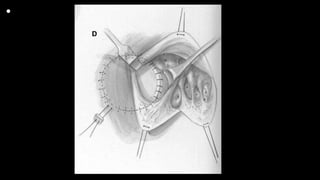

• Figures 1 and 2 Standard cardiopulmonary bypass with direct

bicaval cannulation is achieved, even in the neonate, at

a systemic temperature of 28°C to 32°C (cannulas removed for

clarity). A vent is placed through the right superior

pulmonary vein and cold blood cardioplegia administered after

aortic cross clamping. A right atriotomy is made parallel

and close to the right atrioventricular groove. Placing the incision

in this location assists in the exposure by elevating the

anterior wall of the right ventricle and tricuspid valve with the

stay sutures inserted along the atriotomy. The ventricular

septal defect is visible behind the anterior leaflet of the tricuspid

valve. Traction sutures are placed in the anterior and

septal leaflets of the tricuspid valve. In the neonate, a patent

foramen ovale is generally left open, but is closed in older

infants